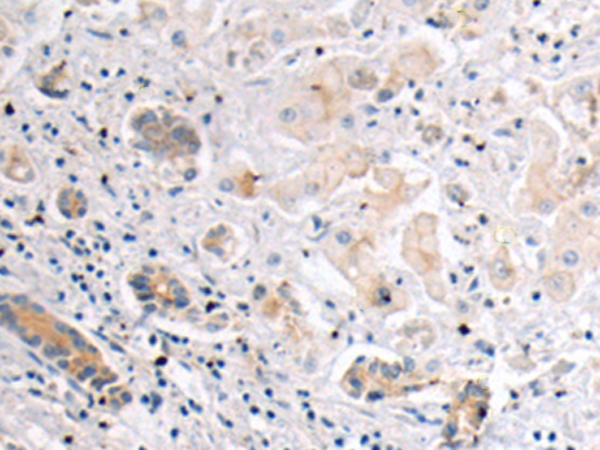

分类: 科研抗体货号: P10649别名: BETA3AR应用: IHC反应种属: Human